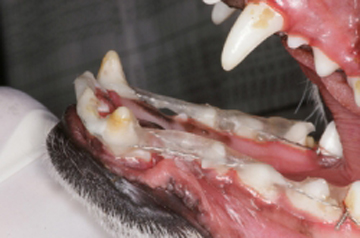

En el caso de la gingivitis, se clasifica según el tejido presente como “Gingivitis simple” en la cual la encía libre y papilar se encuentra hiperémica y sangrante; “Gingivitis hiperplásica” cuando la encía se encuentra con un aumento muy considerable en su tamaño y presenta un tejido inflamatorio hiperémico, sangrante e hiperplásico; y “Gingivitis hiperplásica fibrosa” cuando la encía está muy aumentada de tamaño y con una gran cantidad de tejido fibroso que se caracteriza por no ser hiperémico ni sangrante, sino que es de color rosa muy claro e inclusive hasta blanco y muy duro. Una de las características de las gingivitis hiperplásica y la gingivitis hiperplásica fibrosa es la presencia de bolsas periodontales falsas, ya que al medir la profundidad del surco este aparece aumentado, pero es debido al aumento del tamaño de la encía libre y papilar y no a la perdida de estructura ósea alveolar.